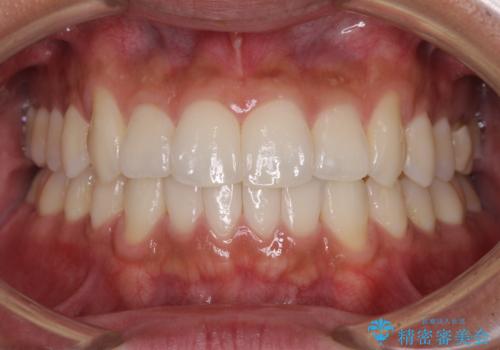

- 抜歯した歯や抜歯が必要と思われる歯を放置したため、奥歯に不快を感じているとのことで来院された患者様です。

また、下顎前歯にはスペースがあり、コンポジットレジンでスペースを閉じている状態だったので、前歯のスペースを解消しつつ、奥歯にスペースを獲得するよう矯正治療を行うこととしました。

奥歯1歯分を動かすには時間がかかるため、矯正治療には思いの外時間がかかりました。

痛みのある奥歯は必要に応じて根管治療を行い、左下インプラントは角化歯肉の移植により清掃性を向上させ、気になっていた部分をしっかりと改善させることができました。